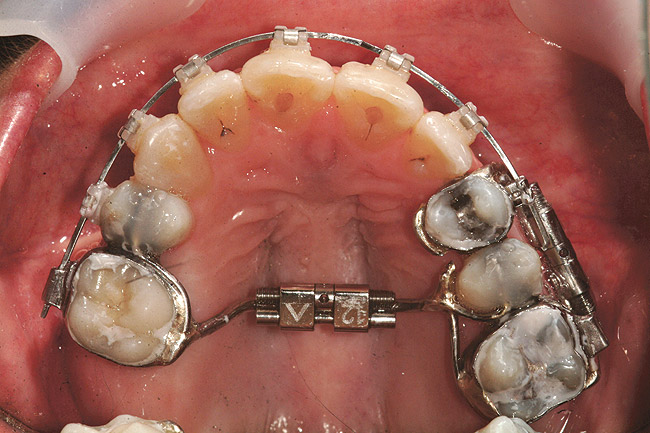

Fig 18 (through Fig 21). Note lack of alveolar development from congenitally missing Nos. 24 and 25. Surgical procedures after 5 months of orthodontic alignment included single-tooth osteotomies Nos. 6 to 11 and Nos. 21 to 28 and buccal corticotomies on all other teeth. Anchorage plate was stabilized to piriform rim.

Fig 20. Note lack of alveolar development from congenitally missing Nos. 24 and 25. Surgical procedures after 5 months of orthodontic alignment included single-tooth osteotomies Nos. 6 to 11 and Nos. 21 to 28 and buccal corticotomies on all other teeth. Anchorage plate was stabilized to piriform rim.

Fig 21 (and Fig 20). There is significant lateral dentoalveolar expansion of arches and alveoloskeletal correction in maxillary and mandibular anterior regions. Alveolar bone volume was increased in lower anterior to create optimal implant sites and establish ideal interincisal function and stability.